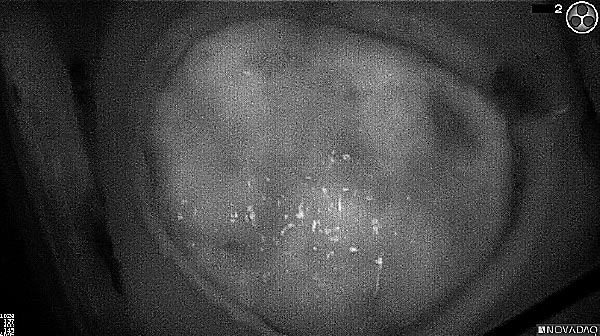

Near-infrared (NIR) labeled EGFR antibody, panitumumab-IRDye800, is systemically infused in high-grade glioma patients and specifically binds to tumor cells across the blood-brain barrier to improve intraoperative visualization during MRI-guided resection.

Skull Removed

Brain Exposed

Tumor Visible

Tumor Removed

White light

Fluorescence (heat map)

Fluorescence (black and white)

As the tumor was located beneath the brain surface (as indicated in presurgical MRI), minimal fluorescence was detected through the intact dura. The tumor lied beneath the area (dashed line: expected incision path) where faint fluorescence signal showed up on the brain surface. A clear fluorescence signal was visible in the tumor when the surgeon reached the tumor (dashed circle). Very little fluorescence remained in the wound bed after surgical removal of the tumor. You may also want to read the 2019 interview with Dr. Li and Dr. Rosenthal on novel imaging technologies to identify brain cancer.